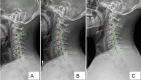

We present a case report of a patient suffering from chronic low back pain (CLBP) and chronic non-specific neck pain (CNSNP), both of which were caused and complicated by a physically demanding occupation, a history of mixed martial arts, and lumbar scoliosis. Improvements in patient-reported outcomes (PROs) and radiographic findings were observed following conservative spine rehabilitation. The patient, a 34-year-old male, had experienced chronic spine pain, particularly CLBP and CNSNP, for several years. He reported severe pain and increasing disability after a recent neck injury sustained while practicing jiu-jitsu. Radicular pain, along with numbness and tingling, was noted in the right upper extremity, extending to the first three digits, and there were also altered sensations and temperature changes in both feet. He described sharp, pinching mid-back pain and worsening disability due to the persistent pain, which led him to seek manual manipulative chiropractic spine therapy, though he reported little benefit from it. The patient had relied on over-the-counter pain medications for many years without achieving long-term pain and disability relief, and these medications were no longer used following treatment. Chiropractic BioPhysics® (CBP®) spinal structural rehabilitation protocols were used to improve coronal and sagittal balance, as well as paraspinal muscular strength, addressing posture, mobility, and related aspects. These protocols include postural exercises, postural Mirror Image® traction, and postural spinal manipulative therapy. All PROs improved, with a near resolution of all initial symptoms of chronic spine pain. Outcomes measured included disability indices and health-related quality of life (HRQoL) indicators. Radiographic parameter improvements were significant, demonstrating improved coronal and sagittal balance as a result of the treatment. Following 30 in-office treatments, administered three times per week for 10 weeks, initial outcomes were reassessed. The patient then received 13 in-office treatments periodically over one year, and all initial outcomes were repeated. The improvements remained stable over time. A 26-month follow-up found that the improvements were sustained over a very long period without additional treatment after the 13-month examination. Chronic spine pain, specifically CLBP and CNSNP, is a significant source of suffering and contributes substantially to the global burden of disease. Improvement in HRQoLs, PROs, and objective spine parameters are desirable clinical outcomes. Our case report documents objective improvement in lumbar scoliosis and spine pain, which is rare in conservative studies. This successful treatment of chronic pain with long-term follow-up contributes to the growing evidence supporting conservative, non-surgical treatments for CNSNP and CLBP. Successful management of chronic spine pain was observed in a patient undergoing CBP® treatment. The treatment was designed to address abnormal sagittal and coronal postural balance and radiographic abnormalities indicating spinal misalignment and reassess progress in PROs, as well as objective and subjective HRQoL measures, both following treatment and 13 months later. However, larger studies are needed to draw firm conclusions regarding the efficacy of this treatment for chronic pain.